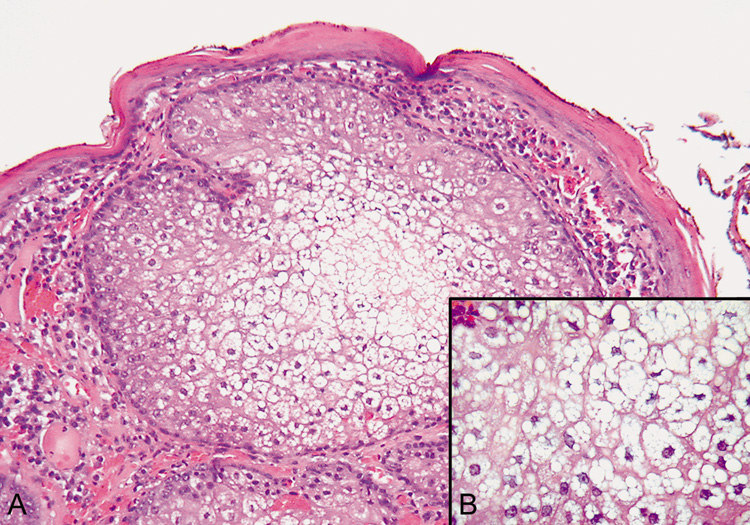

Xanthelasma commonly occurs in older individuals with normal serum cholesterol. However, in younger patients, it should alert the physician to look for hypercholesterolemia. Soft, yellowish papules and plaques are most prominent on the lower lids and cheek but may be seen on the upper lids. Histologically, dense clusters of foam cells are found in the superficial dermis. Intracellular lipid gives a vacuolated appearance (Fig. 12).

Fig. 12. Xanthelasma—A. Clinical photograph of xanthelasma showing typical distribution of the xanthomatous nodules on the eyelids. B. High-power photomicrograph of many multinucleated foamy xanthoma cells (hematoxylin and eosin stain). (Photos courtesy of William Morris, M.D.)